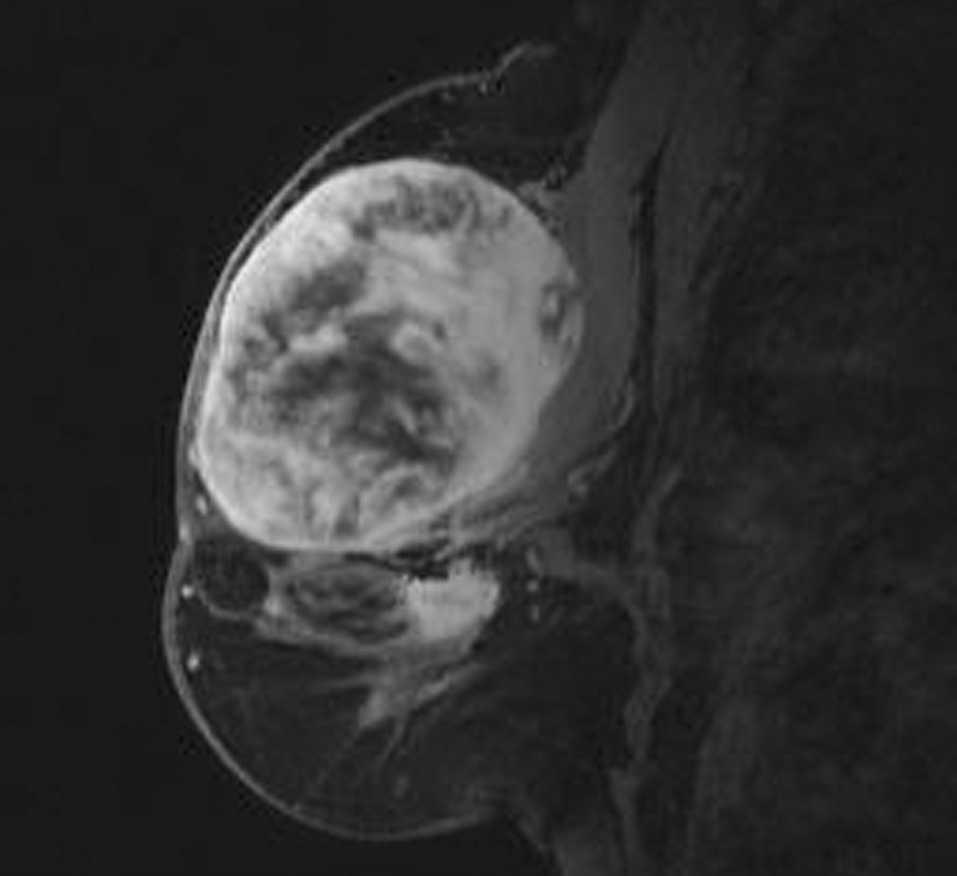

Una paciente de 56 años acude a consultas externas de nuestro centro por presentar desde hace varias semanas una gran masa, bien circunscrita, en la mama izquierda sin signos de afección dérmica. La exploración no identifica otros nódulos sospechosos; el tamaño tumoral es de 8 x 6 cm, de consistencia pétrea, que ocupa ambos cuadrantes superiores. No se palpan nódulos axilares, supraclaviculares o infraclaviculares. La mamografía muestra una masa única de 6 x 6 cm, de contorno redondeado sin otros hallazgos de interés (fig. 1A y B). La ecografía muestra una única masa sólida de ecogenicidad heterogénea, de 6 x 3,4 x 5,8 cm (fig. 2). La resonancia magnética (RM) muestra 2 nódulos de similares características, el mayor ocupa los cuadrantes superiores de la mama izquierda y mide 6 x 6 cm; el menor se sitúa por debajo de nódulo antes descrito y mide 1,8 x 2,3 cm, y no puede visualizarse al revisar las mamografías ni las ecografías. El comportamiento dinámico de ambas masas es indicativo de malignidad (fig. 3). Se realiza una biopsia con aguja gruesa que muestra un tejido fibroso, con características neoplásicas, muy indicativo de miofibrosarcoma mamario. Se realiza una mastectomía simple. La inspección macroscópica de la pieza muestra una masa de 5,5 cm con unas paredes nacaradas, lisas y parcialmente bien definidas con zonas que infiltran los tejidos adiposos vecinos. No se aprecian áreas de necrosis. Microscópicamente, se aprecian numerosos fascículos de células fusiformes separados entre ellos por amplias bandas colágenas, entre las cuales se encuentran pequeños grupos de adipocitos (figs. 4 y 5). En general, el pleomorfismo nuclear es muy acusado y la mayoría de las células presenta núcleos fusiformes, aunque algunas muestran núcleos redondos con abundante citoplasma eosinófilo. El índice mitótico es de 6 figuras por 10 campos de gran aumento. El estudio inmunohistoquímico muestra una intensa positividad de las células tumorales para el sarcoma mamario y vimentina; numerosas células muestran positividad para CD68. No se aprecia positividad para desmina, citoqueratinas ni antígeno de la membrana epitelial. El diagnóstico histopatológico final es de miofibrosarcoma mamario de grado II con márgenes libres de infiltración tumoral.

Figura 3. Resonancia magnética que muestra 2 nódulos de similares características.